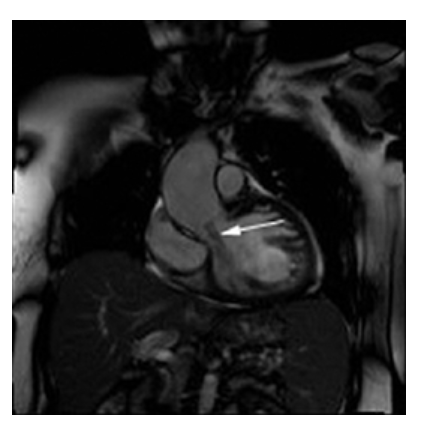

Aortic Regurgitation. Coronal oblique view shows moderate jet (dark, signal void) emanating from the aortic value into the left ventricle (arrow). There is also dilatation of the ascending aorta.